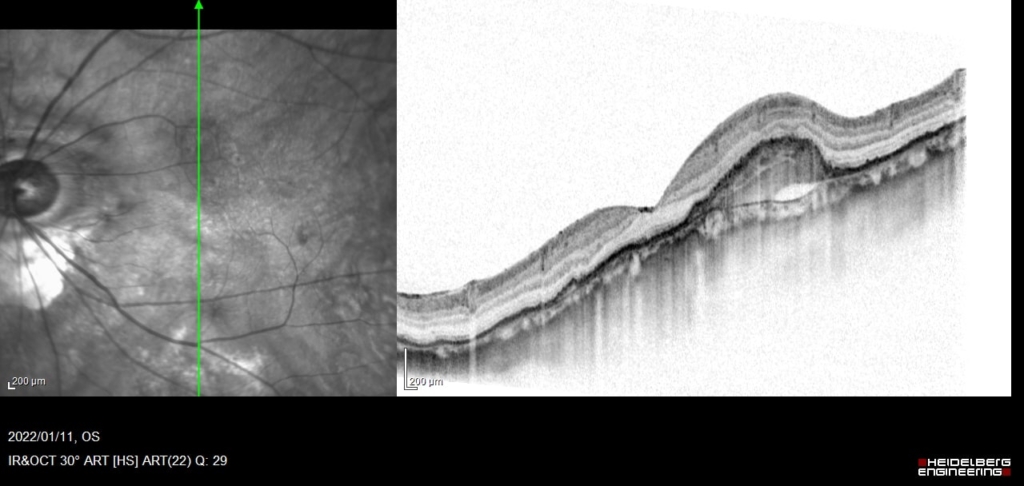

RPE下に広がるCNVとBruch膜の間に間隙が生じており、同部位でBruch膜が後方に偏位している。間隙は浸出液の貯留による。

硝子体注射2日後に出血

CNVの活動性の指標として、PED内部のCNVとBruch膜に間にBruch膜を後方に押すように生じる間隙や、PED自体の増大は注意が必要。